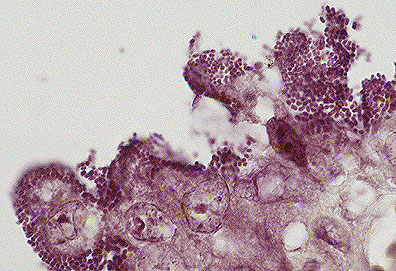

Alveolar proteinosis in a SCID mouse. Note the abundant eosinophilic material in the alveoli (HE, 400X, 93K)

In humans, pulmonary alveolar proteinosis (PAP) is an uncommon disorder in which the alveoli are filled with lipoproteinaceous material, including surfactant. It has been observed as a spontaneously occurring lesion in the lungs of CB.17 scid/scid mice and scid/scid-beige mice and resembles PAP in humans. Also, PAP has been reported in granulocyte-macrophage colony-stimulating factor (GM-CSF)-deficient C57BL/6 mice (knockout mice). Light microscopy shows varying amounts of a homogeneous to granular proteinaceous material in alveolar spaces. This material is eosinophilic by hematoxylin and eosin stain and is periodic acid-Schiff (PAS)-positive. Ultrastructurally, the material resembles surfactant. Immunohistochemical staining of lung tissue, and Western blot and ELISA of lavage fluid shows marked increases in surfactant proteins SP-A and SP-B in comparison to controls. The cause of this disease in humans and mice is unknown but appears to involve a disruption of surfactant homeostasis.

AFIP Diagnosis: Lung: Proteinaceous bodies, intraalveolar, multifocal, numerous, with mild multifocal lymphoplasmacytic interstitial pneumonia and alveolar histiocytosis, SCID mouse, rodent.

Conference Note: Pulmonary alveolar proteinosis (PAP) has been reported in many species including humans, mice, rats, hamsters, guinea pigs and goats. It occurs spontaneously and in association with many systemic diseases. Grossly, PAP presents as white to gray, round foci which frequently elevate the pleural surface of the lung. These foci often expand and coalesce with time.

There are two histologically distinct presentations of PAP. The first, or type I, occurs in humans, SCID mice, and SCID/beige mice. In type I PAP, there is accumulation of granular deposits of surfactant lipoproteins within the alveoli and little or no inflammatory response. The second, or type II PAP, is characterized by the presence of large numbers of alveolar macrophages with abundant cytoplasmic accumulations of lipoproteins. Type II PAP occurs in the rat, hamster, and guinea pig and can be induced in the rat by inhalation of silica dusts or intraperitoneal injection of chlorphentermine.

The abnormal accumulation of lipoproteins in the airways causes impaired alveolar gas exchange, leading to exercise intolerance, dyspnea, and fatigue. Pulmonary alveolar proteinosis can affect experimental results in laboratory animals, possibly confounding or invalidating studies.

The etiology of PAP has not been determined. The finding that GM-CSF deficient mice and beige mice (which have impaired natural killer cells and neutrophils due to a defect in the lysosome granule system) develop type I PAP implicates ineffective removal of surfactant by macrophages. Overproduction of surfactant by type II pneumocytes is also considered a possible pathogenesis for the development of PAP.